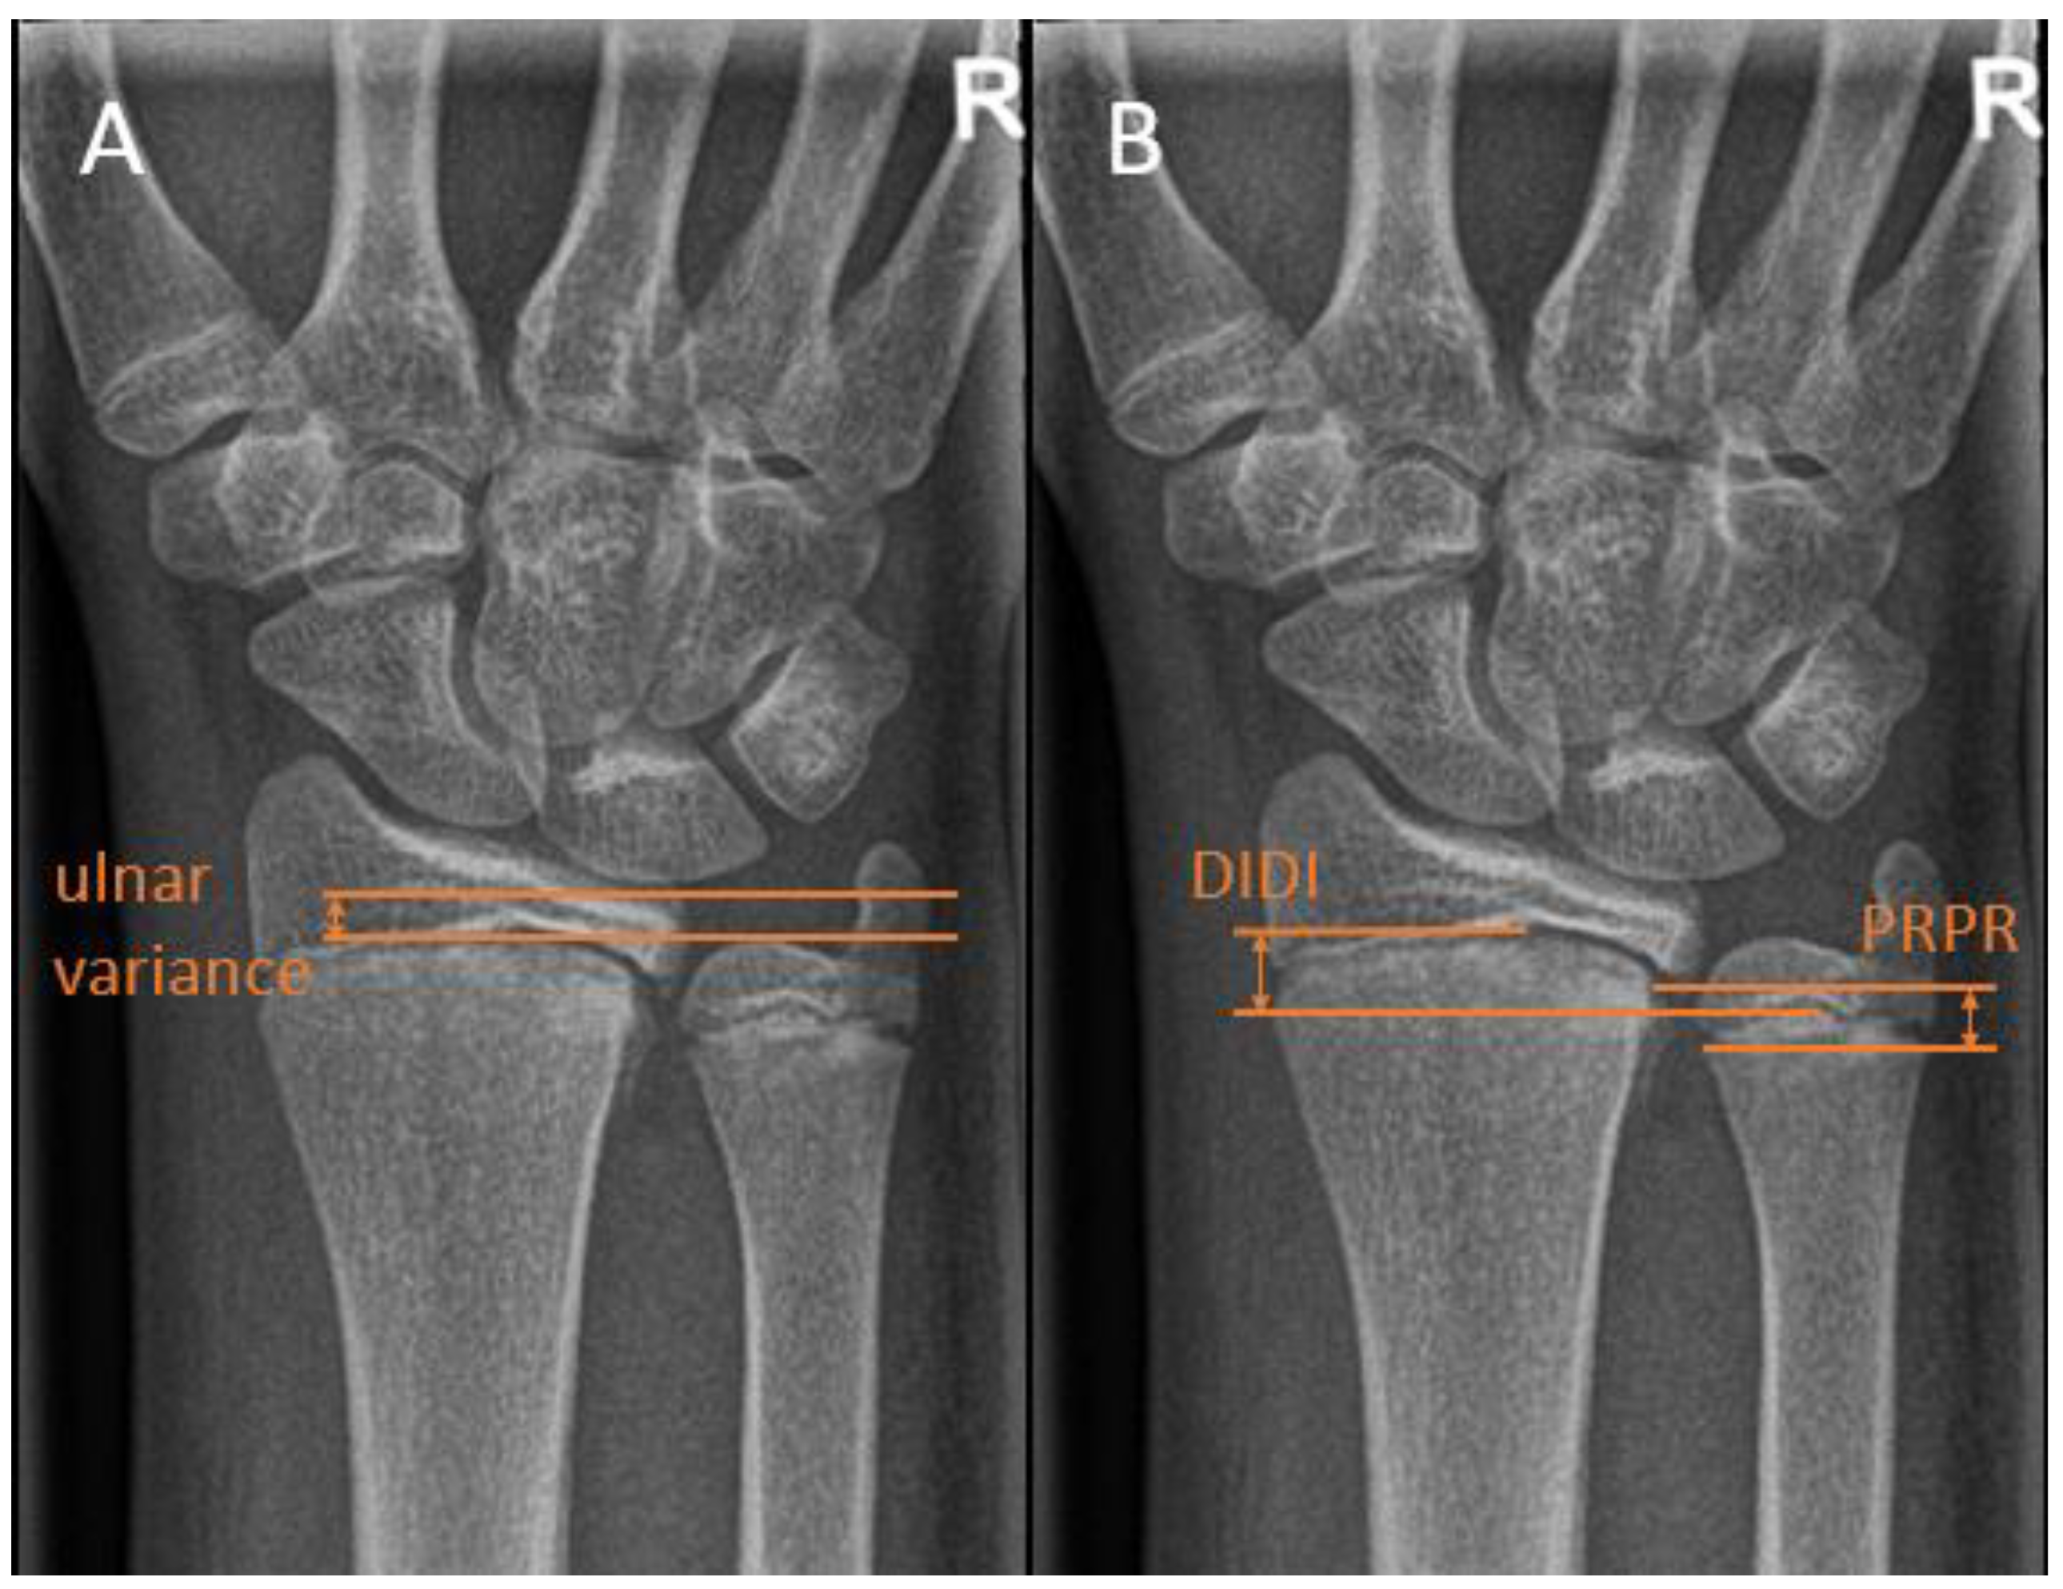

Ulnar variance, or Hulten variance, can be positive, negative, or neutral. In positive ulnar variance, the ulna is longer than the radius. Conversely, in negative ulnar variance, the radius is longer than the ulna. In neutral ulnar variance, both the articular surfaces of the radius and the ulna are at the same height. Ulnar variance is independent of the length of the ulnar styloid process, which may also vary.

There are multiple ways of measuring the ulnar variance. In the method of perpendiculars, a line is drawn perpendicular to the longitudinal axis of the radius and through the most distal ulnar part of the radius. The distance between the adjacent distal cortical rim of the ulna relative to this line is then measured as the variance [17] (Figure 4A). In the method as described by Hafner et al. [18], a line is drawn perpendicular to the longitudinal axis of the ulna, touching the most proximal prominent point of the ulnar metaphysis on the radial side. Secondly, a line is drawn on the radius perpendicular to its longitudinal axis touching the most proximal point of the radial metaphysis on the ulnar side. Ulnar variance is then defined as the distance between these lines. In the literature, these distances are referred to as “Proximal–PRoximal distance [17]. Conversely, the variance can be measured using the distance of the most distal points of the radial and ulnar metaphysis. This method is referred to as “Distal–DIstal” distance. (Figure 4B).

Kox et al. investigated the difference between the above-stated methods for measuring ulnar variance in a group of 350 healthy children and adolescents. It was found that the Hafner method was the preferred method for children with unfused growth plates or those younger than 13 years, and the adapted perpendicular method was recommended in children with fused growth plates or those 14 years and older [17].

Ulnar variance changes with wrist position and during clenching of the wrist. It is more positive during pronation and becomes more negative during supination. In addition, a clenched fist results in a relatively more ulna plus compared with a neutral grip. Therefore, obtaining only a PA-view with a neutral grip may underestimate maximal variance, and obtaining clenched fist view radiographs can be a useful addition [15].

Figure 4. Distal ulna radiographic reference lines. (A) The Hafner method for measuring ulnar variance. (B) The method of perpendiculars for measuring ulnar variance, with ‘PRPR termed as the two most proximal points of the physis and ‘DIDI’ termed as the two most distal points of the physis.